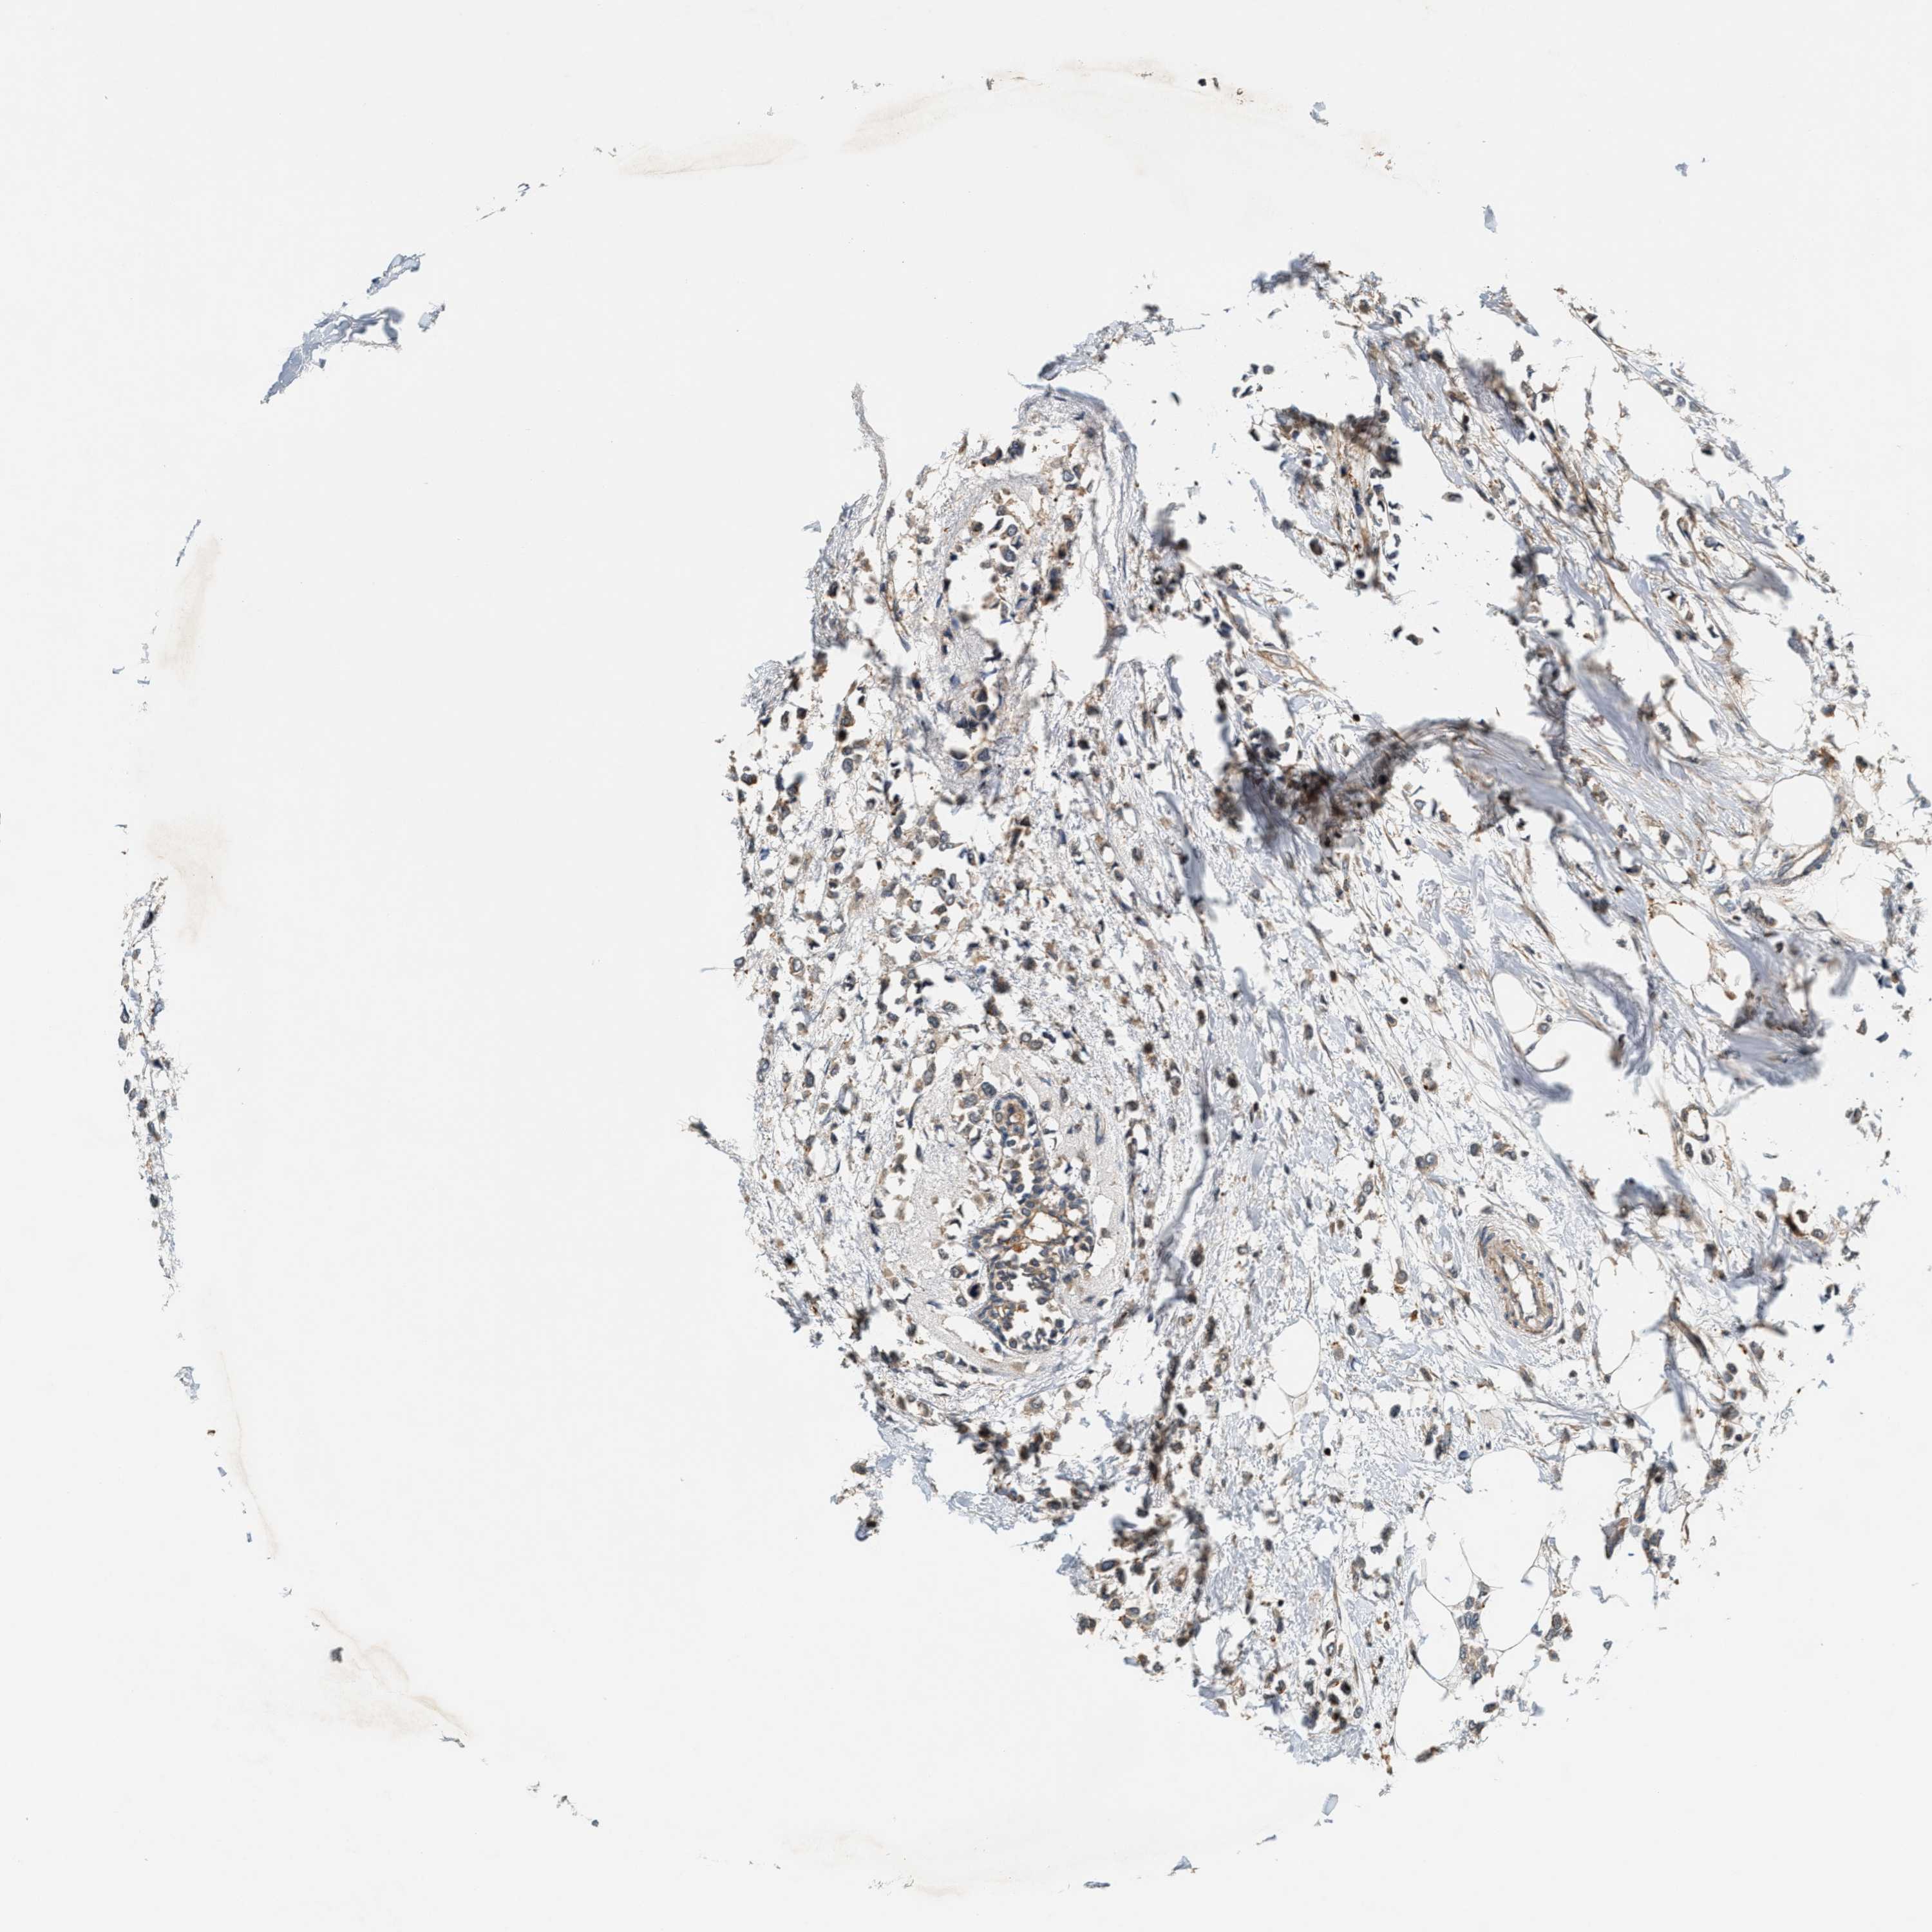

CANCER BREAST CANCER Show tissue menu

BRCA TCGA BRCA VALIDATION PROTEIN EXPRESSION

ANTIBODIES

AND

VALIDATION